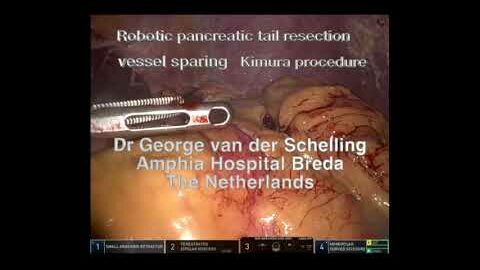

# 209 Robotic pancreatic tail resection Kimura procedure- Dr. George van der Schelling